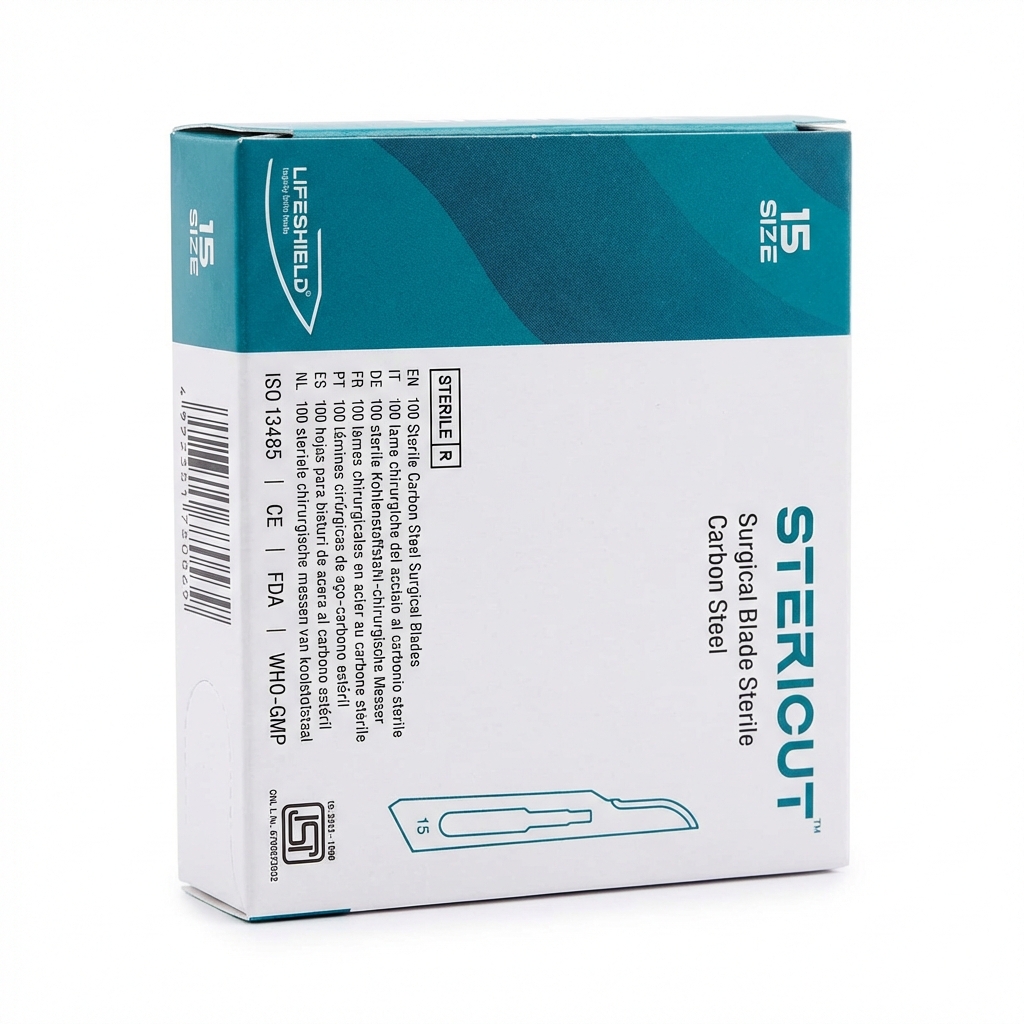

Carbon steel blades gamma radiation sterilized for precision

The LifeShield Sterile BP Surgical Blades come in a pack of 100, providing ample supply for your surgical needs.

An exceptional, highly precise carbon steel surgical blade featuring a classic small, curved cutting edge. It delivers flawlessly clean, controlled incisions for intricate mucoperiorsteal flaps, delicate sulcular contouring, and precise soft-tissue surgeries.